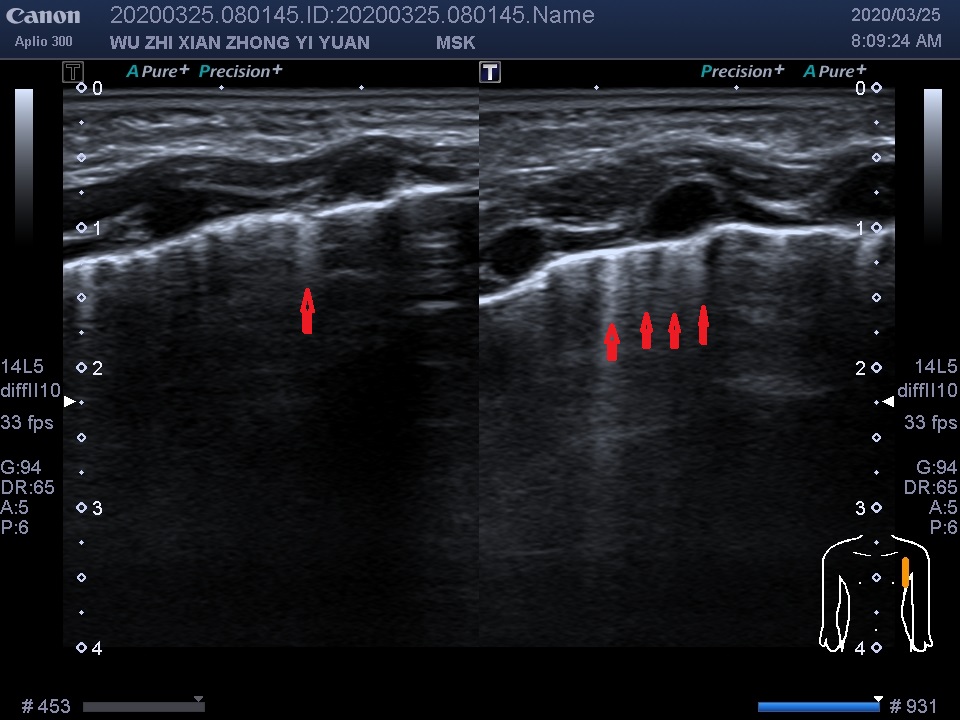

图中所示:红色箭头所指竖线为B线,箭头所指横线为A线,于右肺锁骨中线第2-5肋间,锁骨旁线及腋前线均可探及密集较粗大B线,部分呈“火箭征”,滑线可见,A线显示欠清晰。